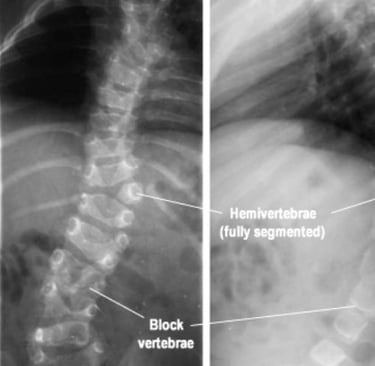

الجنف الخِلقي

ينتج الجنف الخِلقي عن تشوّهات في الفقرات تكون موجودة منذ الولادة، ويحدث نتيجة عدم اكتمال تطوّر العمود الفقري أثناء مرحلة النمو داخل الرحم.